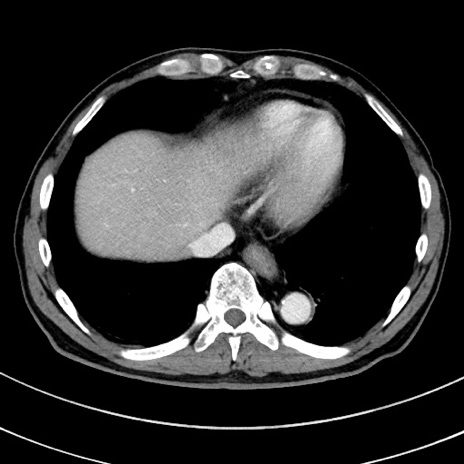

冠状断像

症例8(横断像)

【症例】 60歳代男性

【主訴】 黒色吐物

【現病歴】 4日前から嘔気自覚、2日前の朝食後にも嘔気あり、自分で手で嘔吐反射起こし嘔吐したところ血が混ざっていたため受診。

【既往歴】 5年前汎発性腹膜炎を伴う急性虫垂炎で手術、高血圧、前立腺肥大症、高脂血症

【身体所見】 腹部正中に手術癩痕あり 腹部平坦・軟圧痛なし膨満感あり

【データ】WBC 8400、CRP 4.54